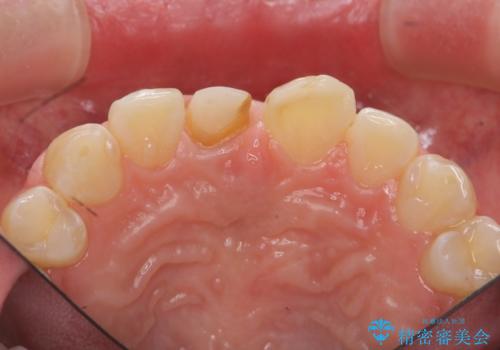

前歯をきれいにしたい ジルコニアクラウンによる審美治療

- 前歯の見た目の改善を求めて来院されました。

ジルコニアクラウンによる審美性の改善を計画します。

失活歯のため捻転を改善し、根管治療は特に希望されなかったのでそのままとしました。

今回失活歯であったため捻転を取り反対側の前歯に揃えて補綴を行うことができました。